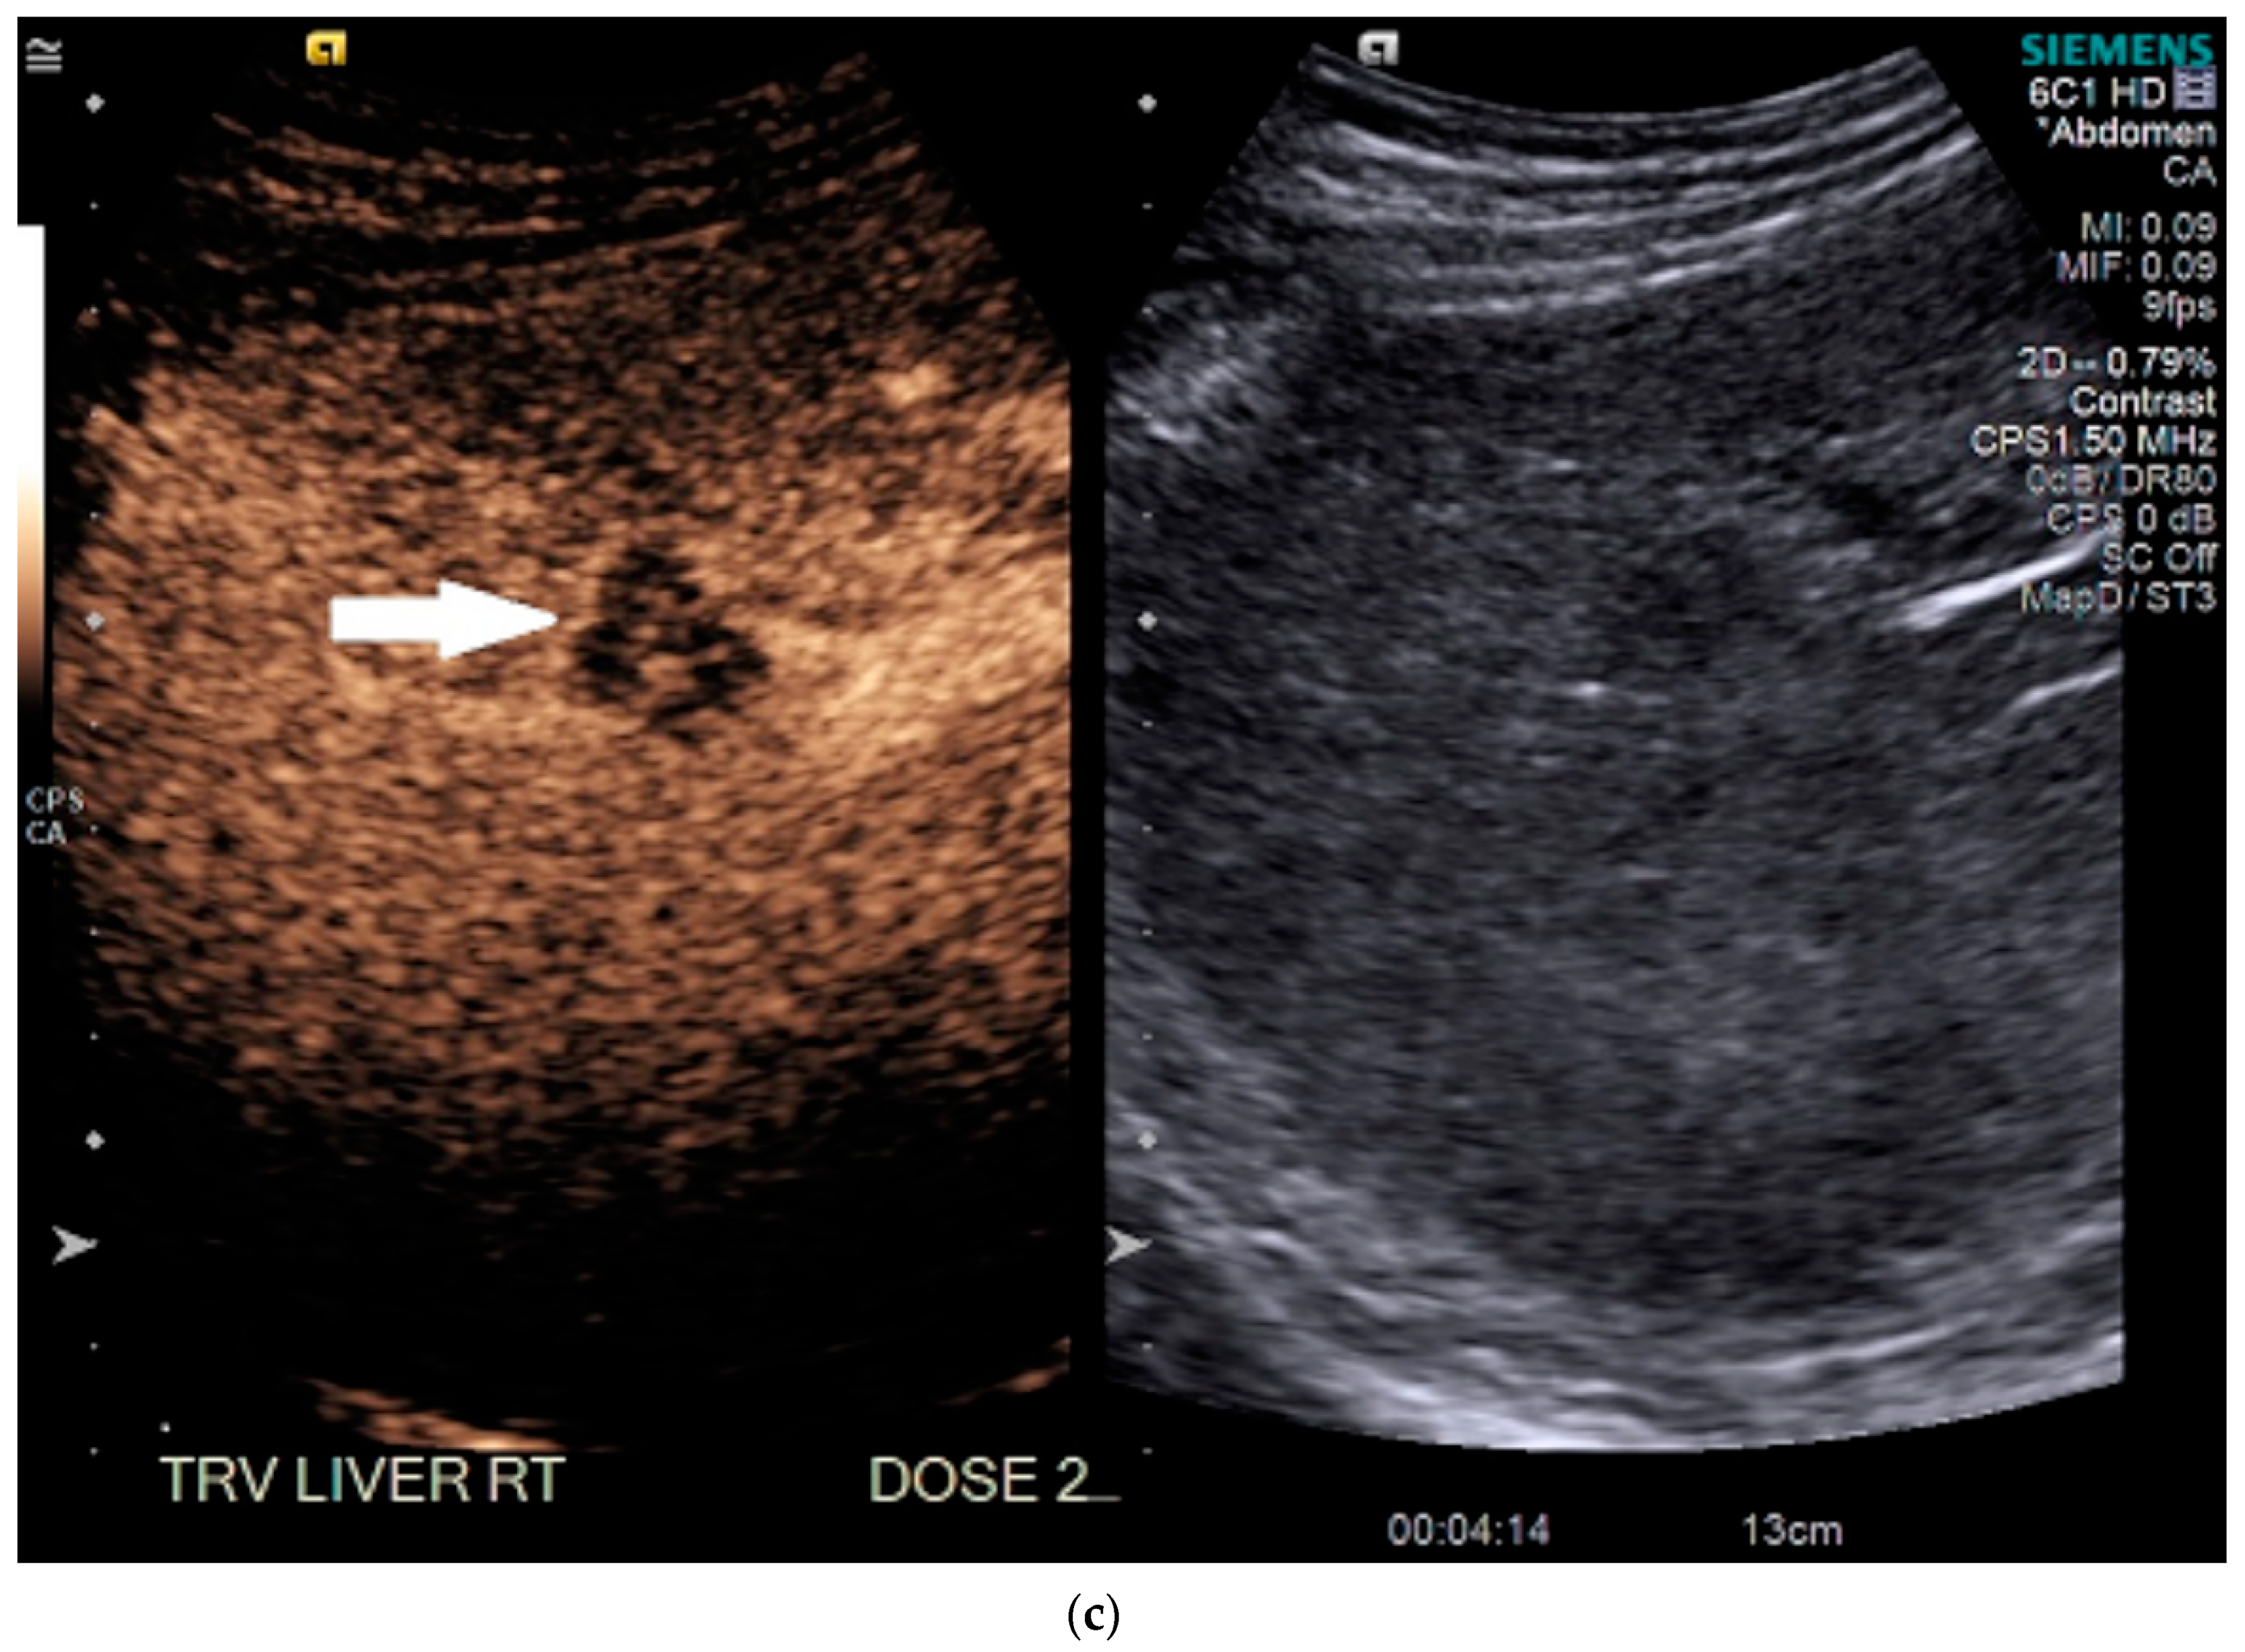

3.2. Case 2